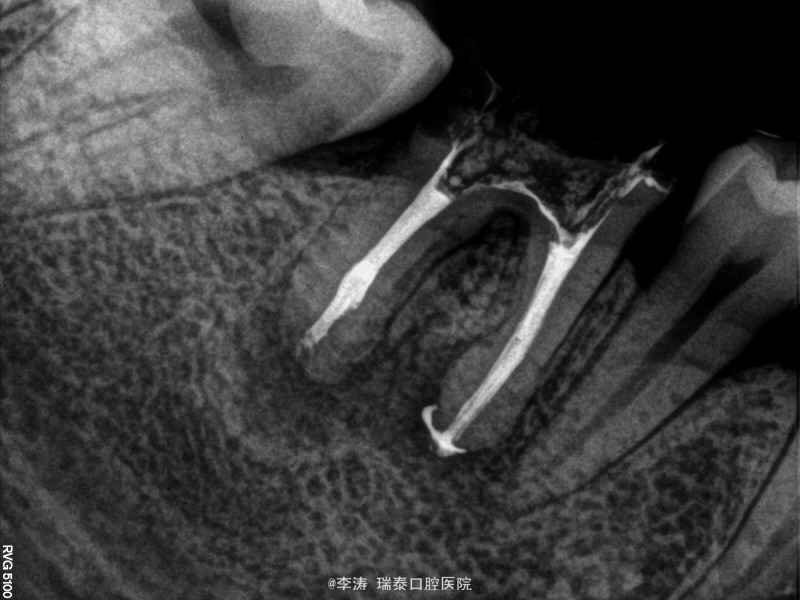

X线片

46牙根尖暗影,

先行46根管治疗,髓底至颊舌侧壁约2.5mm,近远中壁1.5mm,考虑行髓腔固位冠修复

46从片子上看缺损面积较大,而且髓室底较薄,根分歧下有低密度影,对于它的修复时机给你提个建议,建议观察一段时间再修复,不要急于修复。

- 李涛回复徐晓旭:髓底还是完整的,先根管治疗之后观察3个月,看根分叉区炎症会不会消,再考虑修复

46从片子上看缺损面积较大,而且髓室底较薄,根分歧下有低密度影,对于它的修复时机给你提个建议,建议观察一段时间再修复,不要急于修复。

46根充做的很好啊,但髓室底太薄了,无论何种修复预后都存在较大的根折可能性,得注意与患者沟通,避免纠纷。

46片子上看,根分叉处有病变,根分叉处病变是很难愈合的,同时髓室底很薄,所以建议还是分根术,两个根分别打桩联冠修复,前提是根分叉区阴影消失

就片子来看,还是支持46桩核冠修复。

针对46来说,如果预后良好,与16的咬合空间仅1mm,应该说做桩冠比做桩核冠固位效果好。